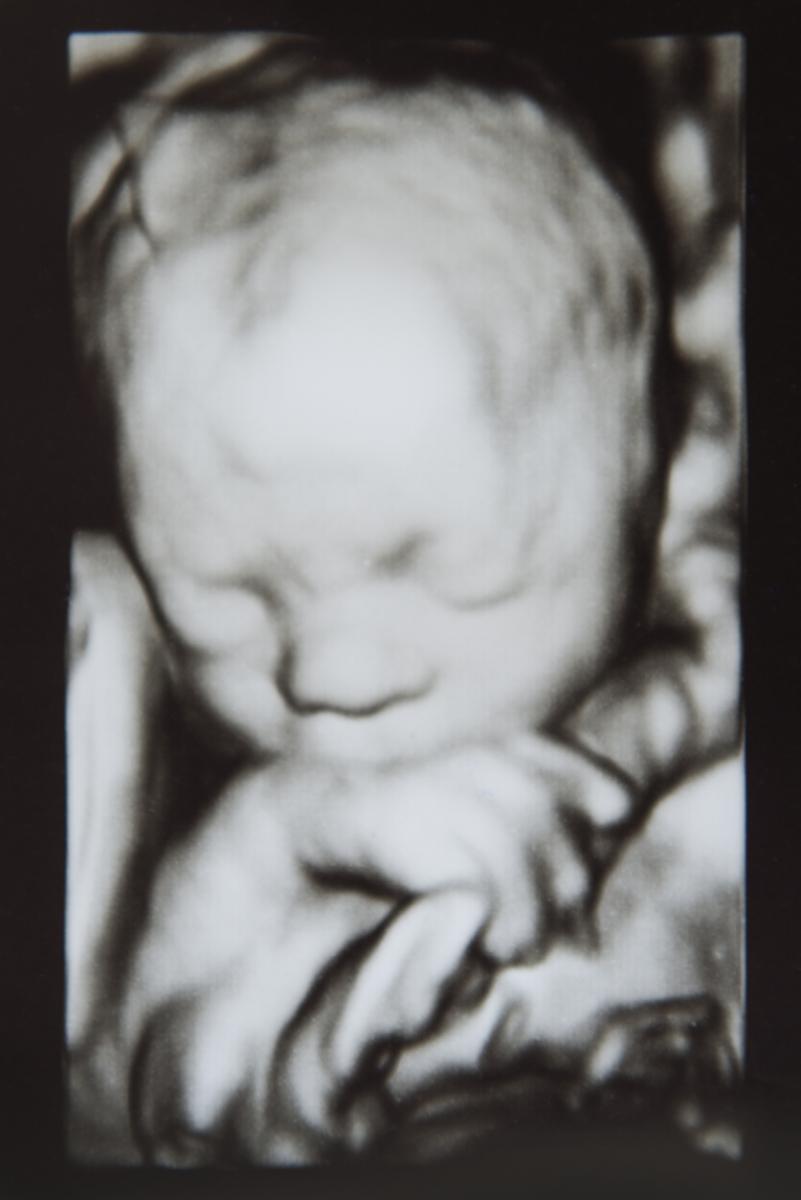

На 30-32-ата седмица, с помощта на 3 или 4D технологии, с точност може да се определи на кой от двамата родители ще прилича бебето.

За състоянието на бебето в утробата може да се съди по мимиките му. Няколко мащабни проучвания сочат, че ако мига, смуче палец, суче, прозява се, отваря очи – то е с по-малък риск да има неврологични отклонения.